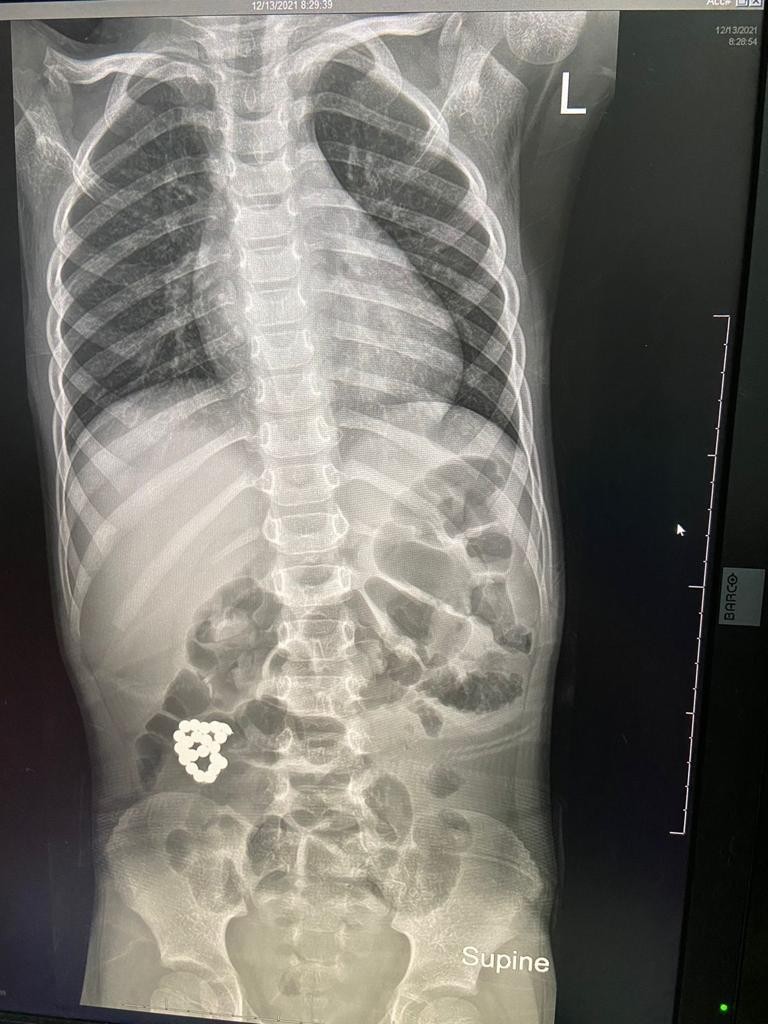

تمكن فريق طبي بمستشفى الملك عبد العزيز بجدة بقيادة بروفيسور جراحة الأطفال الدكتور عمر منصور من إنقاذ حياة طفل في السادسة من عمره، حضر لطوارئ المستشفى يشتكي من ألم في البطن ملازمه منذ ٤ أيام وازدادت الآلام مع الوقت، حيث تم عمل الفحوصات اللازمة، وأظهرت صور الأشعة وجود جسم غريب في الأمعاء.

وعلى الفور تم إدخال الطفل لغرفة العمليات واستخراج الجسم الغريب، كما تضرر جدار الأمعاء، حيث تم استئصال الأجزاء المتضررة  في عملية أستغرقت ساعتين ونصف تكللت بالنجاح ولله الحمد والطفل في حالة مستقرة بفضل الله، في قسم التنويم العادي وحالته في تحسن.